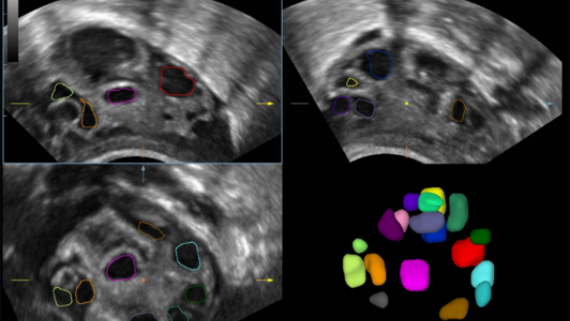

ImĂĄgenes clĂnicas